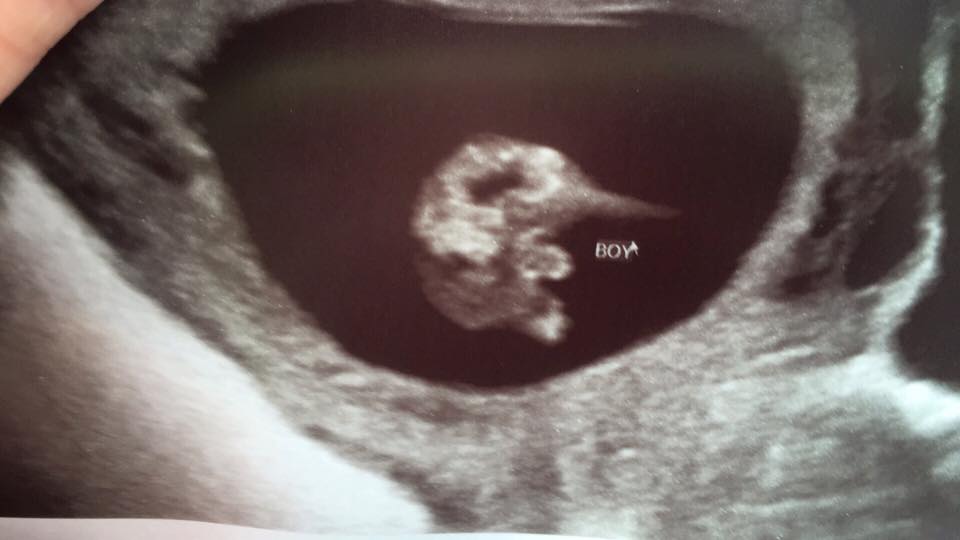

This is the potty shot from 13.4w.

Sonographer said he is 100% sure it's a boy (which i didnt think you could be that early on) but something is telling me the potty shot looks too big and thick to be boy parts.

Is there a possiblity, being so early, that it could still be a girl? I remember my sons potty shot was a lot smaller and easily identifiable as a boy. This makes me so unsure.